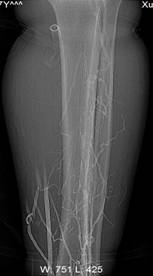

刘××,男,57岁,下肢静脉造影显示混合型DVT,血栓充盈整个左下肢深静脉(图1a~c)。经左股静脉置管后溶栓治疗,10日后血栓完全溶解,再次造影显示左下肢深静脉血流通畅(图2a~c)。